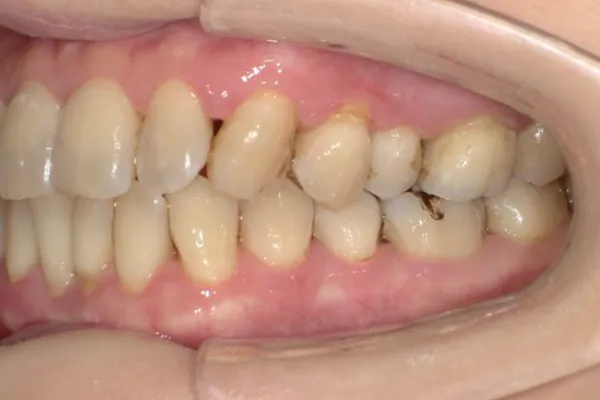

正確な診断

歯周ポケット測定やレントゲン・CT解析など、多角的な検査で歯周病の進行度と原因を正確に把握します。患者さま一人ひとりに最適な治療計画を立て、根拠ある治療につなげます。